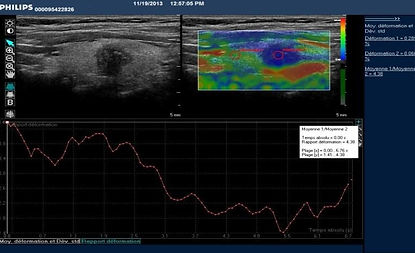

elastografía patológica

elastografía normal

Dos tipos de elastografía cuantitativa y semicuantitativa.